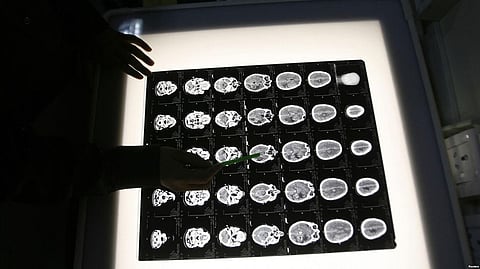

Stephanie Hopper was the first patient in the Duke study. She was diagnosed with glioblastoma eight years ago. She had the tumor removed, but two years later, it returned. The modified virus is directly injected into the brain during surgery. After treatment, Hopper's tumor shrunk to the point where it's barely noticeable in her brain scans, and the tumor is continuing to shrink.